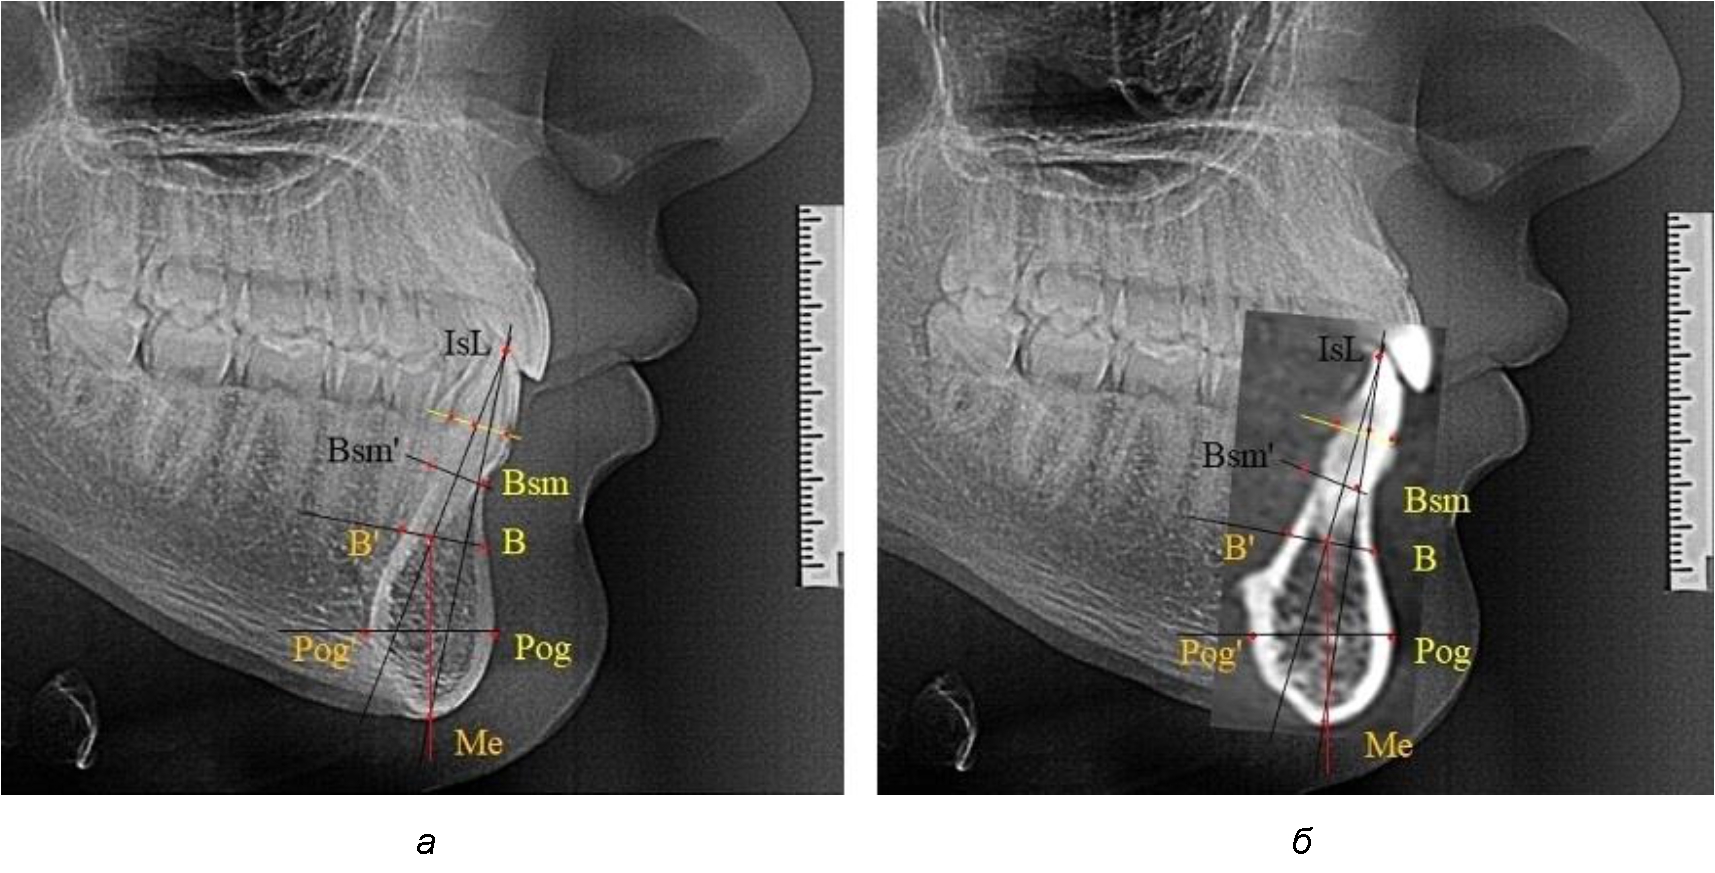

На режущем крае нижнечелюстного резцового сегмента устанавливалась точка, обозначаемая как IsL.

Определяли положение цервикальных точек резцов на вестибулярной и лингвальной поверхностях, которые соединяли цервикальной линией. Условная срединную вертикаль зуба соединяла резцовую точку IsL с серединой цервикальной линии и, как правило, доходила до апикальной точки, которую обозначали как Ap. Линия IsL–Ap определяла высоту зубоальвеолярной части резцового нижнечелюстного сегмента. Определяли высоту коронки и корня зуба. Кроме того, на вестибулярной поверхности зубочелюстного сегмента отмечали точку наибольшей вогнутости альвеолярной части, которая обозначалась как супраментальная точка Downs (Bsm). Измерялось расстояние IsL–Bsm, которое служило для определения проекции супраментальной точки Downs на язычную поверхность сегмента и обозначалась как точка Bsm'.

Проекцию верхушки корня резца на кость обозначалась как точка B нижнего апикального базиса по Schwarz. Соединяли апикальную точку с точкой нижнечелюстного апикального базиса линией, которая доходила до язычной поверхности подбородочного выступа и определяла положение точки B'. Таким образом, в зубоальвеолярной части сегмента выделялись две зоны: верхняя и нижняя, с последующим измерением по вертикали. При этом, как правило, верхняя зона была представлена компактной костной тканью, а в нижней зоне определялось наличие губчатой ткани между компактной пластинкой и стенкой альвеолы.

На нижнем контуре подбородочного выступа определяли положение ментальной точки Me. Линия, соединяющая апикальную точку с ментальной, определяла высоту подбородочного выступа тела нижней челюсти. Высота зубочелюстного сегмента IsL–Ме измерялась от резцовой до подбородочной точки. Вертикальная линия Ap–Me делила подбородочный выступ на две части: переднюю и заднюю (рис. 1).

Рис. 1. Ориентиры для исследования нативных препаратов (а) и рентгенограмм (б) резцового нижнечелюстного сегмента

Сагиттальные размеры зубоальвеолярной части сегмента определялись между точками Bsm и Bsm', в апикальной части сегмента – B и B'. В подбородочной части сегмента из передней выступающей точки подбородка Pog проводили линию перпендикулярно к линии Ар–Ме с определением точки Pog'. Расстояние Pog–Pog' определяло ширину подбородочного выступа.